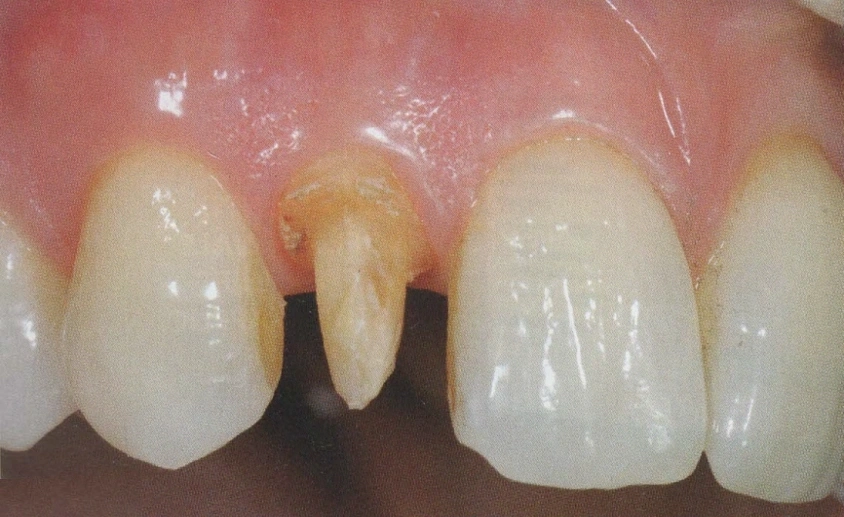

Per l'esecuzione delle impronte vengono usati materiali di prima qualità perchè la precisione delle impronte facilita la costruzione del manufatto e questo è un passaggio fondamentale per la buona riuscita della protesi.

In questo studio vengono eseguite ceramiche di ultima generazione quali la zirconia ceramizzata, le ceramiche estetiche in disilicato senza trascurare le tradizionali metalceramiche. Il disilicato è un materiale altamente estestico che conferisce alla corona protesica un aspetto naturale e con questo materiale si possono creare manufatti con uno spessore molto ridotto.